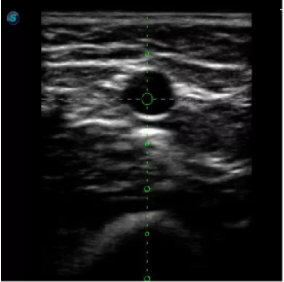

傳統(tǒng)腔內探頭采用直柄設計,在搭配穿刺架使用時,手術空間小,不易操作;生殖專用的曲柄探頭,探頭柄采用彎曲成角度設計,可實現監(jiān)視、取卵兩不誤,搭載穿刺架時,可以清晰顯示穿刺針的進針過程、深度和位置,實時監(jiān)視取卵全過程,保障取卵操作精準與安全。

取卵臨床圖